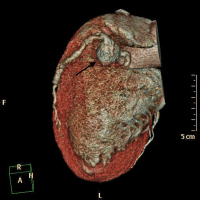

Abbildung 1: Koronar-CT-Darstellung des Aneurysmas

Keywords:

Aneurysma

,

Koronar-CT